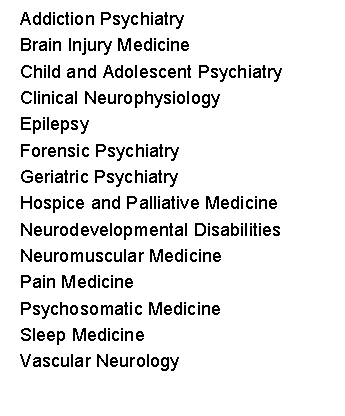

American Board of Psychiatry and Neurology |

American Board of Psychiatry and Neurology |